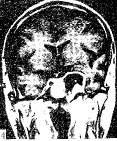

Fig 3 MRI coronal section: A analogical round hyperintense was seen in the left parasellaon T2 WI[TR/TE=2?953/88].

图3 MRI冠状面T2 WI显示左鞍旁类圆形高信号[TR/TE=2953/88]。